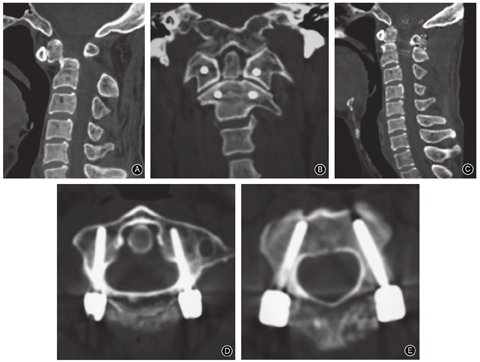

即取寰椎下方侧块内、外缘的中点在后弓上的投影作为进钉点,术中可用探子探及寰椎下方侧块内、外缘;定义螺钉中轴线与正中矢状面形成的角为横向角;螺钉中轴线与寰椎所在平面所形成的角为纵向角,置钉时螺钉横向角为6°~16°,纵向角为3°~5°;选择直径为3.5 mm,长度为21.7~30.5 mm的螺钉。

寰椎(探查法)准确置钉的关键:①通过简易方法确定后弓上的进钉点;②以寰椎后结节所在的解剖位置为坐标系进行研究,得出矢状面夹角(横向角)和寰椎所在平面夹角(纵向角),为此进行了应用解剖学研究[11]。实际应用时探查下方侧块的内、外缘以确定后弓上的进钉点,纵向角应用寰椎后弓和侧块移行部的下表面进行矫正,在寰椎后弓和侧块移行部上、下表面插入神经剥离子以保护上方的椎动脉和下方(寰枢椎之间)的静脉窦,采用磨钻在进钉点至侧块后方按得出的横向角、纵向角对移行部开路,然后用开路探子沿既定方向进入侧块内探查四壁,螺钉直径已固定(3.5 mm),长度由探查确定。若移行部在矢状位上过窄(女性常见),开路后寰椎后弓处于人为"骨折"状态而漂浮。

我们提出在寰椎采用探查法[11]、在枢椎采用直视法[9,10]。寰椎新的参考系选择相对独立,而且规避了上述方法的不利方面,同时明显地降低了操作难度;在术中寰椎下方侧块内外缘均可用探子探及,切实可行。